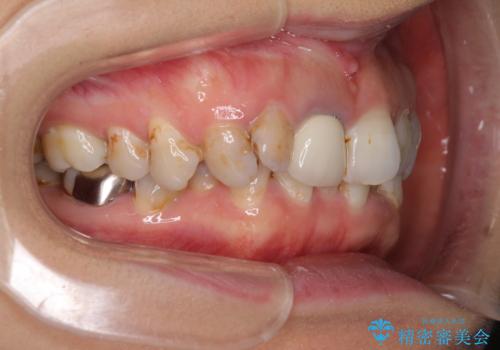

- 前歯の歯並びやむし歯治療の跡、奥歯の銀歯を気にして来院された患者様です。

インビザラインによる矯正治療の後に虫歯や銀歯をセラミックにて補綴することとしました。

前歯のむし歯治療の跡や奥歯の目立つ銀歯がなくなり、明るい口元になりました。